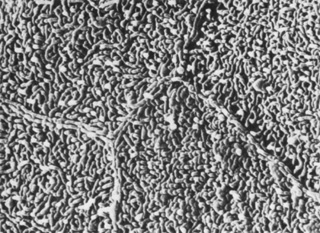

The corneal epithelium is the anterior-most cell layer of the cornea (Fig. 1). It is typically several cell layers thick, consisting of the apical cell squamous layer, the multilayered, polygonal-shaped wing cells beneath the apical layer, and the posterior-most layer of basal cells (Fig. 2). The wing cell layer is two or three cells thick in the central cornea, but tends to be four to five cells thick in the periphery. In total, the epithelium is approximately 50 μm thick in the central human cornea.

Fig. 2. Full-thickness electron micrograph of corneal epithelium. Note the cell shape change with depth, the variation of cell membrane interdigitation, and the intracellular differences between cell types. S, apical surface cells; W, wing cells; and B, basal cells. Also note the microvilli seen along the apical membrane of the surface cells (3,620×). Inset: Epithelium (E) overlies a thin, dense basement membrane (arrow) with no discernible laminar appearance (periodic acid-Schiff [PAS] stain, 330×). (Courtesy of Drs. Rodrigues, Waring, Hackett, and Donohoo.)